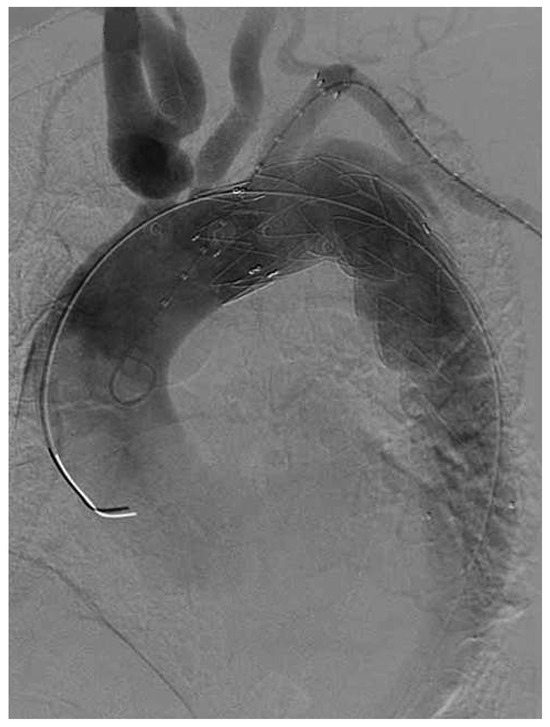

Endovascular Treatment of a Complex Type B Aortic Dissection

by Wen-Dong Li, Qing-You Meng, Li-Wei Zhu, Wen-Bin Wang, Ye-Qing Zhang, Cheng-Long Li and Xiao-Qiang Li

Aortic dissection is a rare disease with high morbidity and mortality, especially when involving multiorgan malperfusion such as lower extremity and visceral ischaemia. Revascularisation should be performed to restore perfusion immediately. We report a case of acute Stanford type B aortic dissection complicated [...] Read more.

Aortic dissection is a rare disease with high morbidity and mortality, especially when involving multiorgan malperfusion such as lower extremity and visceral ischaemia. Revascularisation should be performed to restore perfusion immediately. We report a case of acute Stanford type B aortic dissection complicated by lower extremity, renal and superior mesenteric ischaemia. The right iliac artery was occluded because of compression of the false lumen, resulting in thrombosis. The patient was successfully treated with endovascular treatments, including thrombus extraction and iliac artery, superior mesentic artery and aortic stenting combined with fenestration. Full article